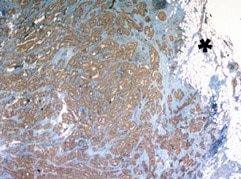

E‑Selectin/CD62E in Human Brain. E-Selectin/CD62E was detected in immersion fixed paraffin-embedded sections of human brain (occipital cortex) using 10 µg/mL Mouse Anti-Human E-Selectin/CD62E Monoclonal Antibody (Catalog # BBA16) overnight at 4 °C. Before incubation with the primary antibody tissue was subjected to heat-induced epitope retrieval using Antigen Retrieval Reagent-Basic (Catalog # CTS013). Tissue was stained with the Anti-Mouse HRP-DAB Cell & Tissue Staining Kit (brown; Catalog # CTS002) and counterstained with hematoxylin (blue). View our protocol for Chromogenic IHC Staining of Paraffin-embedded Tissue Sections.